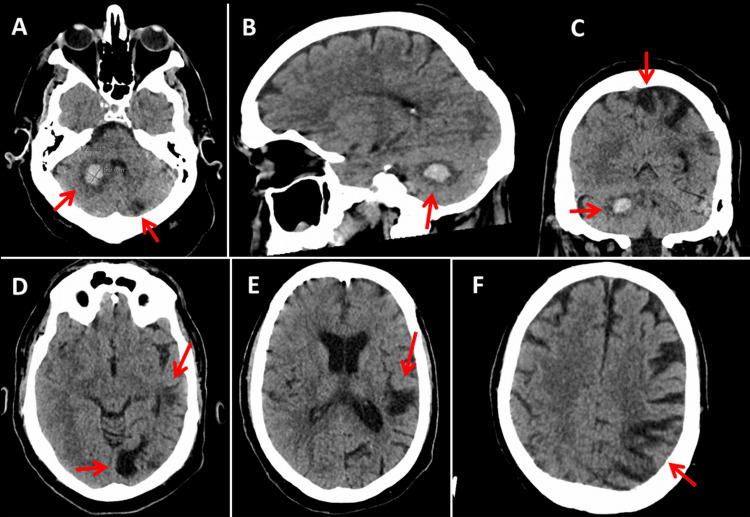

The dual coagulation disorder hereditary protein S deficiency and activated protein C (APC) resistance, which clinically manifests with recurrent venous thrombosis and multifocal ischemic stroke, has only rarely been reported in the same patient. The patient is a 54-year-old male with a history of recurrent, asymptomatic ischemic stroke or transient ischemic attack (TIA) since age 14 and four episodes of deep vein thromboses (DVT), two complicated by pulmonary embolism, attributed to hereditary protein S deficiency and homozygous factor V Leiden mutation. In addition, the medical history was positive for obesity, previous chronic alcoholism, smoking, gynecomastia with left breast resection, arterial hypertension, hepatic steatosis, and cholecystolithiasis. Because of low compliance, long-term oral anticoagulation with phenprocoumon from the age of 38 was replaced by dabigatran (300 mg/d) after another stroke with bleeding at the age of 54. In summary, the simultaneous presence of two hereditary coagulation disorders can lead to multiple venous thromboses and recurrent ischemic stroke. An appealing therapeutic option in poorly compliant patients with these two hereditary clotting defects is the replacement of long-term anticoagulation with a vitamin K antagonist (VKA) by a direct oral anticoagulant.

双重凝血障碍——遗传性蛋白S缺乏症和活化蛋白C(APC)抵抗,临床上表现为复发性静脉血栓形成和多灶性缺血性中风,同一患者中这种情况鲜有报道。该患者为一名54岁男性,自14岁起有复发性无症状缺血性中风或短暂性脑缺血发作(TIA)病史,并有4次深静脉血栓形成(DVT)发作,其中2次并发肺栓塞,病因是遗传性蛋白S缺乏症和纯合子因子V莱顿突变。此外,病史显示患者有肥胖、既往慢性酒精中毒、吸烟、男性乳房发育伴左乳房切除术、动脉高血压、肝脂肪变性和胆囊结石。由于依从性差,38岁起服用苯丙香豆素进行的长期口服抗凝治疗,在54岁再次中风并伴有出血后,改为服用达比加群(300毫克/天)。总之,两种遗传性凝血障碍同时存在可导致多发性静脉血栓形成和复发性缺血性中风。对于这两种遗传性凝血缺陷且依从性差的患者,一个有吸引力的治疗选择是用直接口服抗凝剂替代维生素K拮抗剂(VKA)进行长期抗凝治疗。